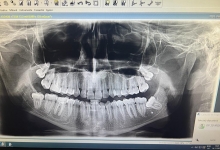

In urma unui consult dentar, medicul stomatolog stabileste primii pasi pentru implantul dentar: examen radiologic si analize de sange. La examenul radiologic se obtin informatii exacte despre cantitatea de os care urmeaza sa primeasca implantul dentar. Tot acum se poate stabili daca este nevoie de o eventuala aditie osoasa. Implantul se lasa in os intre 4 – 6 luni.

In acest timp are loc procesul de integrare in formatiunea osoasa. Succesul integrarii implantare este dat de catre formarea unei cantitati suficiente de celule osoase in jurul implantului dentar. In functie de necesitatile functionale sau estetice ale pacientului, urmeaza etapa protetica de realizare a lucrarilor de ceramica sau zirconiu. Implantul dentar este foarte important deoarece oasele maxilare se resorb, iar structura fetei incepe sa se modifice. In lipsa dintilor, atat masticatia cat si estetica au de suferit. O igiena necorespunzatoare, fumatul, bruxismul, etc., sunt factori de risc care duc la deteriorarea implantului. In perioada urmatoare dieta pacientului trebuie sa fie moale si la temperatura camerei.